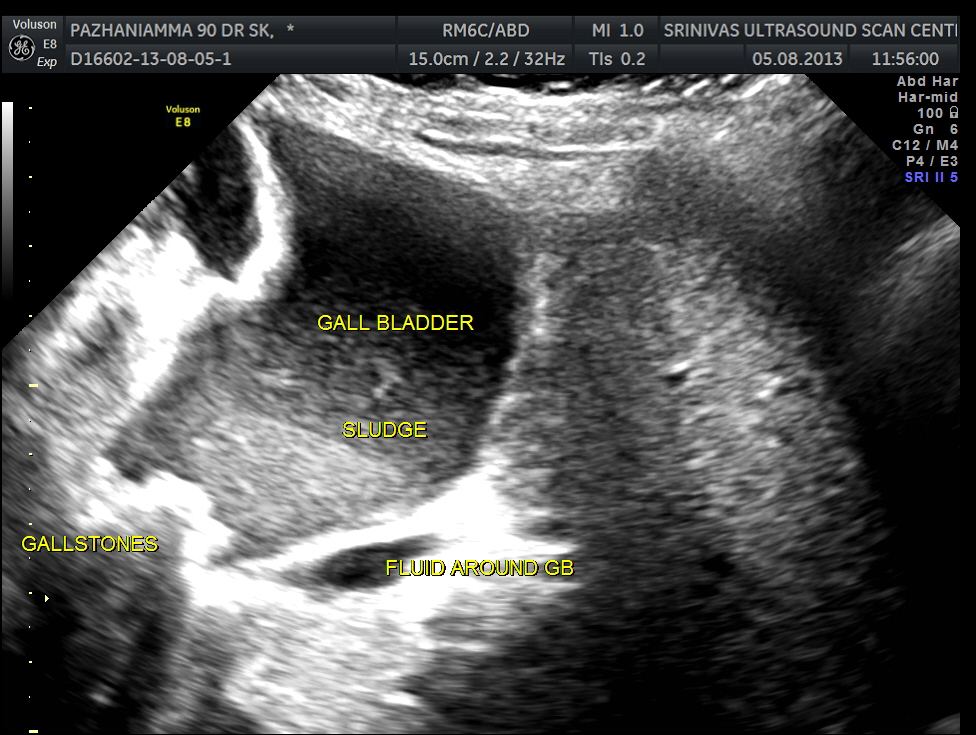

grossly distended gallbladder , with sludge and gallstones and fluid around the gall bladder.

SUB DIAPHRAGMATIC COLLECTION , PROBABLY LOCULATED WAS ALSO SEEN. MINIMAL RIGHT PLEURAL EFFUSION WAS ALSO SEEN.

The diagnosis was : acute calculous cholecystitis , cystic duct stones causing a rupture and fluid collection around the GB and loculated sub diaphragmatic collection with reactive mild right pleural effusion . Endometrial fluid collection needed further evaluation.